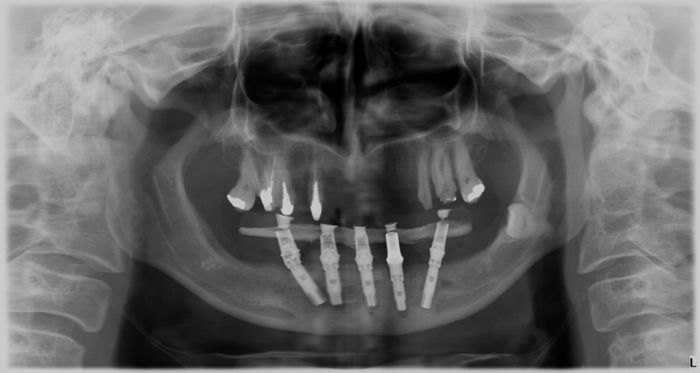

Raio -x inicial em 2014 - Clínica Cliniface

Raio -x inicial em 2014